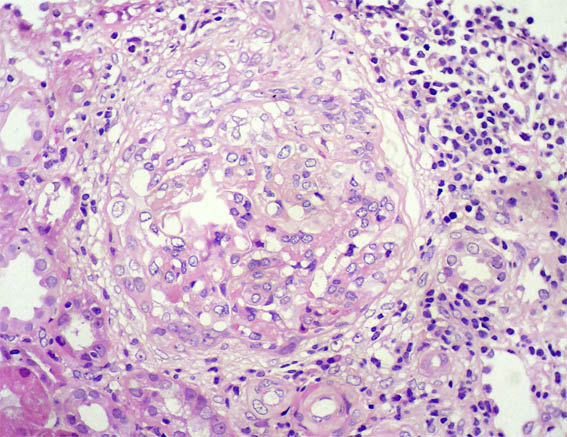

Figure 3. H&E, X400.